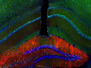

Our skull may look and feel solid but it's actually made up of 28 separate bones that fuse together during development. Having multiple junctions allows the skull to squeeze through the birth canal and then keep up with rapid brain growth. If this process is not perfectly orchestrated, however, children can be born with serious deformations. Cleft palates, which affect one in 700 newborns, are a case in point, caused when the two arch-like plates in the roof of their mouth fail to come together in the womb. Left with a hole in their palate, children can develop speech and feeding problems. The central pin-shaped blue region shows this gap in the skull of a mouse lacking a specific protein implicated in palate formation. In healthy animals with this protein, this space does not exist as the surrounding bones (coloured in pink) close in and fuse together before birth.